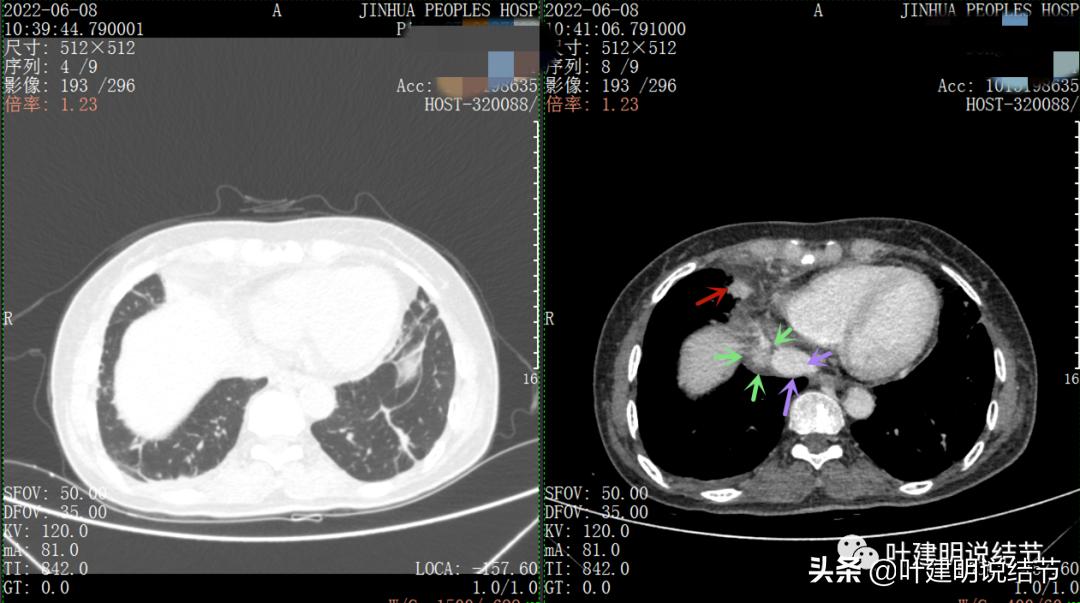

再来看看她的CT增强图像:

以下图片左侧是肺窗,右侧是纵隔窗。红色箭头示病灶,桔色箭头示无名静脉,黄色箭头示支气管,砖色箭头示上腔静脉,蓝色箭头示主动脉,紫色箭头示肺动脉。

病灶胸顶较高位置就出现了,在无名静脉水平

无名静脉略受压

病灶纵隔胸膜侧非常光滑,说明来源于纵隔